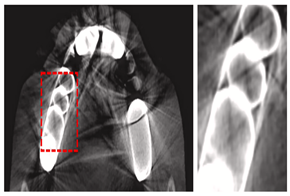

| Cone-beam Computed Tomography (CBCT) | [19,38,53,64,67,93,97,98,99,100,101,102,103,104] | Endodontics, orthodontics, implant, oral surgery, and oral medicine | ![]() | High resolution 3D volumetric data. |